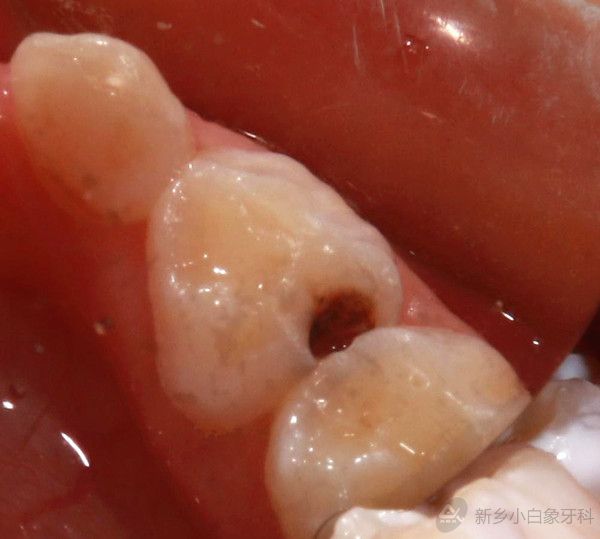

患者齐某某,7岁,家长发现孩子牙齿有洞,影响进食,于8月19日来诊;

口内查:74远中邻面龋坏达牙本质浅层,探诊(-),叩诊(-),温度测验正常,牙龈无红肿;

诊断:74中龋;

治疗计划:74充填术。

1.jpg

治疗前